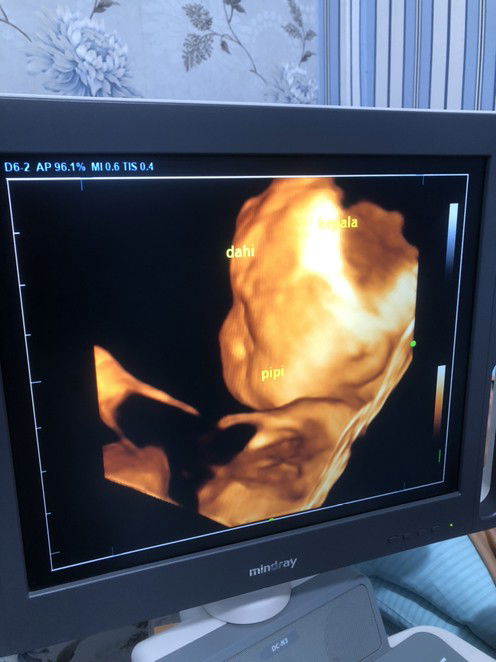

Hehe iyaa dpt si cantik lagii Posisi janin udh dibawah bu, lgi tdrn hadap samping kata dokternya😁 Mangkannya kmrin perutku di goyang2 ma dokternya, biar tanganya ga nutupin wajah

itu USG yang berapa dimensi Bun ?